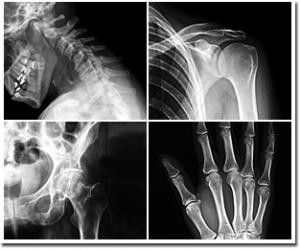

Facultad de Medicina organiza Jornada de Urgencias Traumatológicas

El Departamento de Comunicaciones de la Facultad de Medicina informa que la Cátedra de Traumatología y Ortopedia y alumnos de cuarto curso de esta Unidad Académica, organizan la Jornada de Urgencias Traumatológicas, conjuntamente con la Asociación Médica de Itapuá, auspiciados por la Sociedad Paraguaya de Traumatología y Ortopedia.

Los Temas a ser desarrollados por los Profesionales en esta jornada son los siguientes:

• Traumatismo de Cráneo en Adultos – Dr. Ramiro Ferreira.

• Traumatismo de Cráneo en Niños – Dr. Carlos Leite.

• Artritis – Dr. Damián Escribá.

• Manejo de Lesiones Vascolunerviosas – Dr. Hugo Ferreira.

• Fracturas del Miembro Superior – Dr. Cándido Ojeda.

• Fracturas Expuestas – Dr. Agustín Casaccia.

• Traumatismo de _Columna - Dr. Eduardo Yoshizaki.